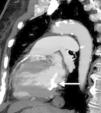

A 79-year-old woman was referred to our department because of suspected angina. The electrocardiogram showed ventricular repolarization abnormalities in the lateral wall. Transthoracic echocardiography showed preserved biventricular systolic function, without wall motion abnormalities, a mitral valve with normal functional area and marked calcification of the annulus, and on the ventricular side a hyperechoic, threadlike and highly mobile mass, protruding into the left ventricular outflow tract, causing a dynamic gradient of 24 mmHg (Video 1). Transesophageal echocardiography (TEE) showed a mass adjacent to the posterior annulus of the mitral valve, measuring about 25 mm×5 mm (Figure 1; Video 2 and 3). Computed tomography confirmed a large calcified mass attached to the ventricular side of the mitral valve (Figure 2). No mass was observed on cardiac magnetic resonance imaging, probably due to its marked mobility. Myocardial perfusion scintigraphy showed evidence of inferolateral ischemia and cardiac catheterization revealed left main and three-vessel disease. Bypass surgery was performed and the intraventricular tumor was removed (Figure 3). Histology confirmed the diagnosis of calcified amorphous tumor (Figure 4).